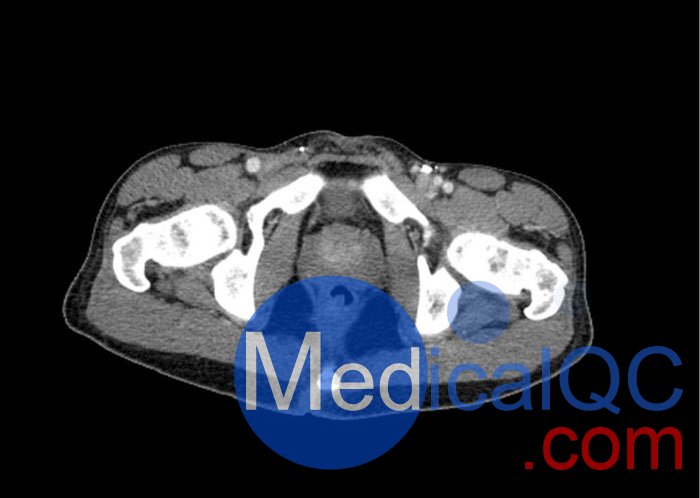

WEK57-01門靜脈期軀干模體,WEK57-01軀干模型模擬了門靜脈期的造影劑增強胸部、腹部和骨盆。它覆蓋了會陰的第二胸椎。

右側有髂淋巴結腫塊。

真實模擬脈管系統、骨骼和軟組織,包括肺、心臟、肝臟、膽囊、胰腺、脾臟、腎上腺、腎臟、胃、小腸、結腸、膀胱和前列腺。

右側髂外淋巴結腫塊。

WEK57-01門靜脈期軀干模體,WEK57-01軀干模型成像效果圖: